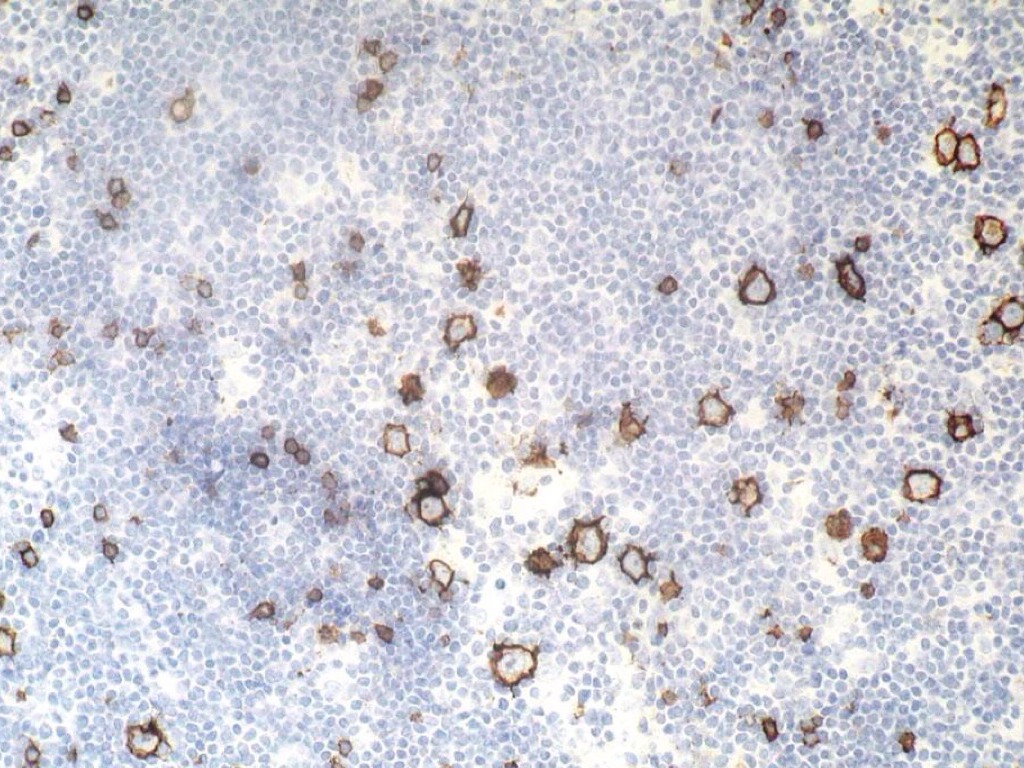

Untitled Slide

CM

• Mezcla de células de Reed-Sternberg con células no neoplásicas

EXPRESAN

• Cd20+\-

• EMA (antígeno epitelial de membrana)

• Cd15

• Cd30

• VEB 40-70%